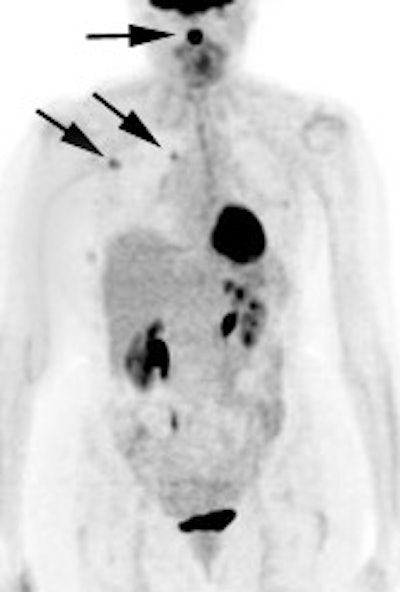

Monitoring response to therapy: The patient shown below had received chemotherapy for treatment of metastatic breast cancer (pre-therapy scan is on the left). The post-therapy scan (right image) demonstrated a very good response to treatment, however, several foci of tracer uptake remained (black arrows) consistent with residual metastatic disease. Further therapy was planned as a result of the PET scan. |